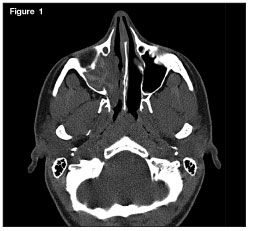

An 18-year-old woman with a history of allergic rhinitis and moderate persistent asthma presented with right-sided nasal congestion of 6 months’ duration. A CT scan showed complete opacification of the right maxillary sinus with increased attenuation of the mucin. Allergic fungal rhinosinusitis, the most common form of noninvasive fungal sinusitis, was the diagnosis.

Image courtesy of Joseph J. Sclafani, MD, Douglas Gottschalk, MD, and Kirk H. Waibel, MD.